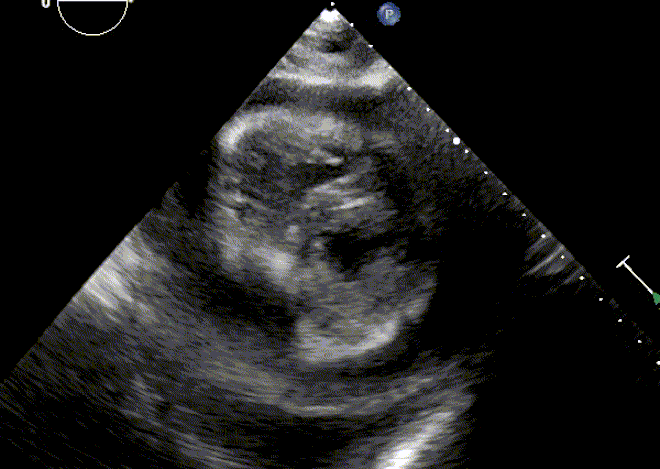

Pericardial effusion and tamponade physiology